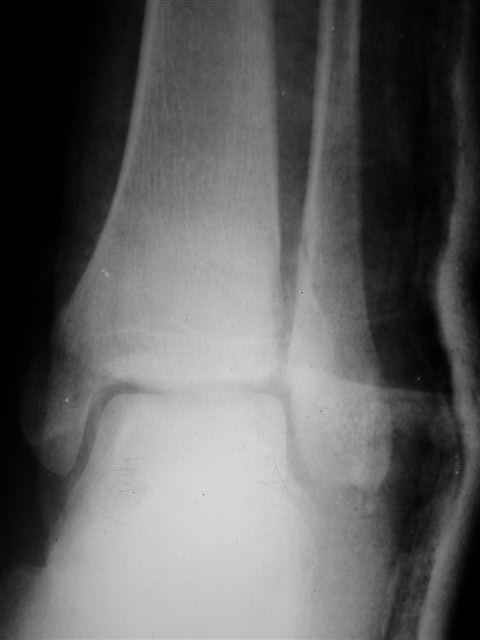

А можно,пожалуйста, более конкретно про повреждение голеностопного сустава?

В первом письме я упомянул о закрытом повреждении правого голеностопного сустава, эверсионно-пронационный механизм травмы - перелом внутренней лодыжки( поперечный, на уровне суставной щели) и отрывной перелом бугорка Chaput. После обработки открытых переломов бедра и большеберцовой кости в эту же сессию перелом внутренней лодыжки фиксировал двумя расходящимися спицами, бугорок Chaput двумя тягловыми винтами 3,5 мм. Раны заживают благополучно. Учитывая повреждение наружной группы мышц, активное разгибание в голеностопном суставе ограничено. Пассивная + пассивно-активная мобилизация голеностопного сустава с физиотерапевтом.